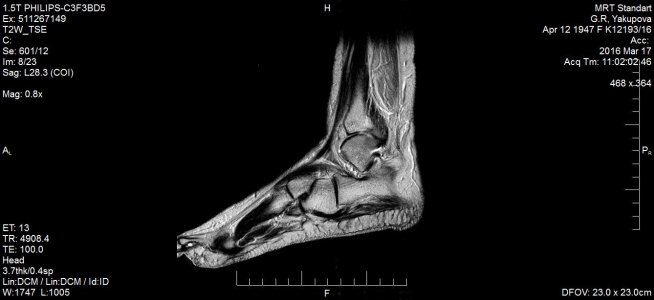

Недели 2 тому назад еще прошла МРТ, написали остеоартроз голеностопного сустава и стопы, минимального синовита голеностопного сустава, краевой косой перелом дорзальных отделов медиальной лодыжки. Что делать дальше? Врач не знает, так как своевременно не наложили гипс, прошло время. Помогите, пожалуйста, что мне делать, чтобы место перелома срослось? Наступать можно полностью на стопу или движение мешает сращиванию?это МРТ снимки